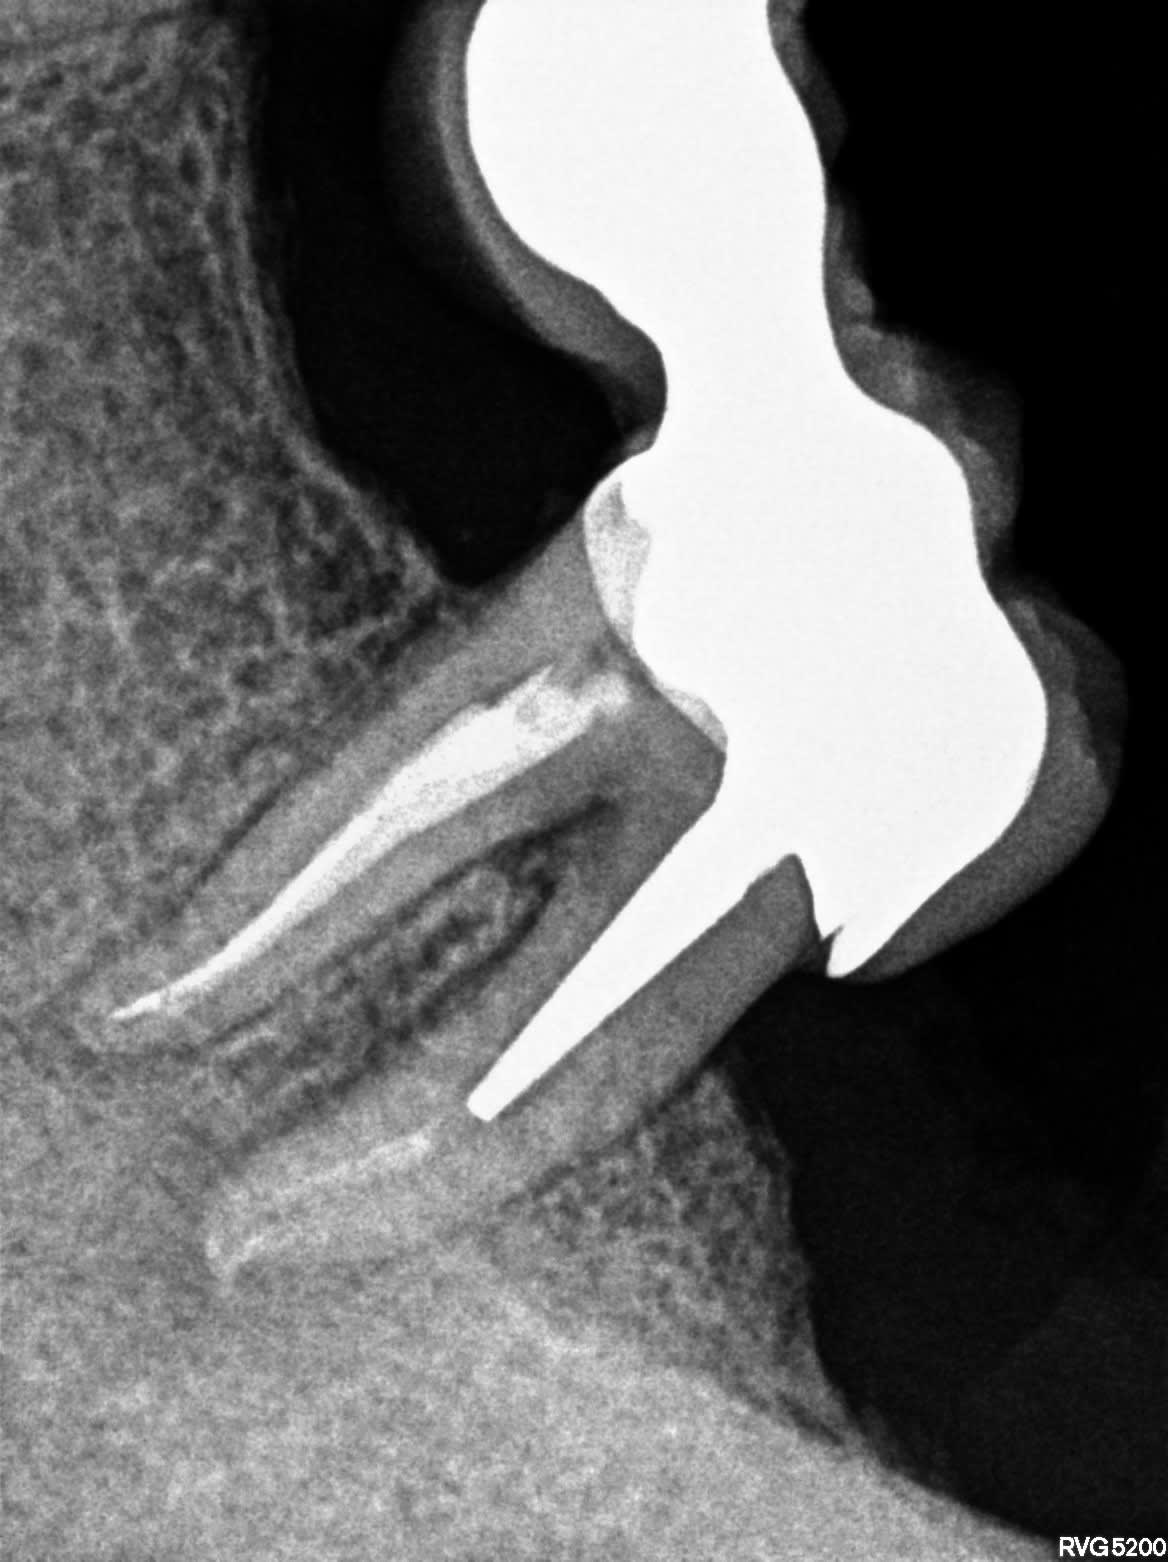

Bon à mon tour... infection à répétition sur cette 37 support de bridge.

Alvéo mésiale distale, curetage et remis la dent avec un cavit. Je croise les doigts!!

R3 m9ooq1 - Eugenol

R5 b27yu7 - Eugenol